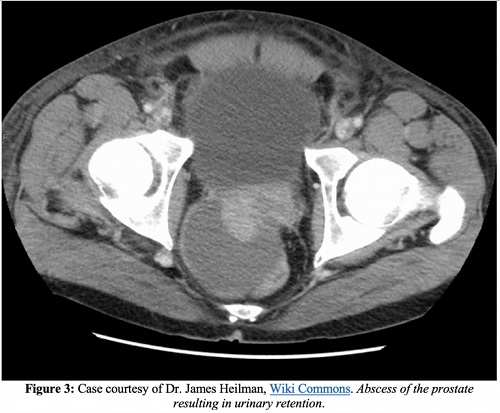

Outre l’endocardite, l’épididymite, la propagation de l’infection aux espaces osseux ou articulaires et le développement d’une prostatite chronique, l’une des complications les plus graves de la prostatite aiguë est un abcès de la prostate. Sur les images tomodensitométriques, les abcès de la prostate apparaissent comme des collections de liquide non rehaussées. Les abcès prostatiques apparaîtront sous forme de zones anéchoïques ou hypoéchogènes à l’échographie transrectale.

La rétention urinaire aiguë est une complication connue de la prostatite aiguë. Certaines sources recommandent de renoncer à l’insertion d’un cathéter de Foley au profit d’un cathétérisme sus-pubien en raison du risque potentiel de rupture d’abcès ou de choc septique. D’autres recommandent un cathétérisme unique avec un test de miction ou un cathéter urétral de Foley de petit calibre à court terme. Une consultation en urologie est recommandée.